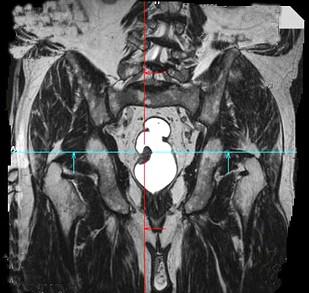

问题 男,70岁,下腹部腹胀、腹痛、排便困难,逐渐加重,MRI示直肠内不规则充盈缺损,请选择最佳诊断结果 ( )

选项 A、直肠转移瘤 B、直肠淋巴瘤 C、直肠癌 D、直肠间质瘤 E、直肠息肉

答案 C